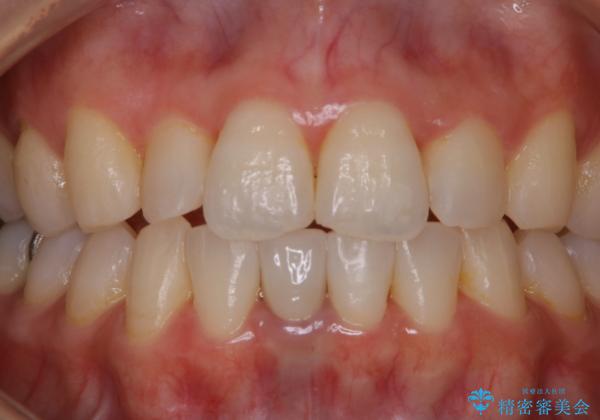

- 夜間の歯ぎしり・食いしばり予防のナイトガードを作成希望とのことで来院されました。しばらくクリーニングも受けていないとのことでPMTC30分コースを行いました。

プラークや歯石により、歯肉が炎症している場合、歯と歯肉の境目が鮮明に型取り出来ないなどがあります。そのため、マウスピースの作成前などには、PMTCで歯の表面の汚れを落とすことで、仕上がりのマウスピースがより精密なものとなります。